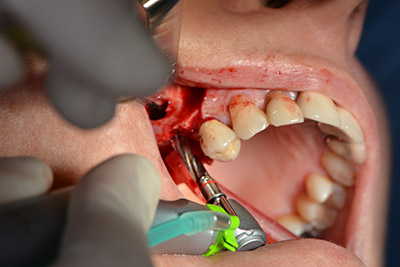

Operatives Vorgehen beim Implantieren

Die klassische Schnittführung (krestal, Entlastung bukkal) und das Präparieren des Mukoperiostlappens erlauben eine gute Übersicht.

In diesem Fall werden Sky Implantate (bredent) verwendet, deren chirurgisches Protokoll die Pilotbohrung mit etwa 1.200/min vorschreibt (Abb. 9).